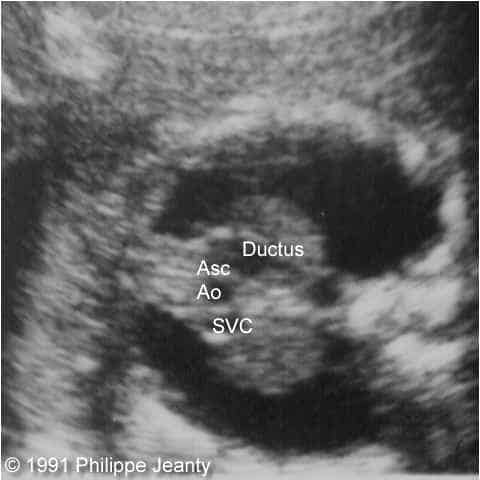

Figure 1: Top (left & right): Axial views of the base of the heart. The relationship between the superior vena cava (SVC), the ascending aorta (asc Ao) and the ductus is seen. Notice the larger size of the ductus compared to the aorta. Middle left: This section, just cephalad to the two previous, demonstrates the common carotids and the SVC. Middle right: Longitudinal section. The SVC is seen entering the right atrium (RA). The ascending aorta is between the SVC and the ductus. It does not connect with the ductus, and bifurcates into the common carotids. Bottom left: Similar view to the previous one. The conection between the ductus and the right ventricle (RV) is demonstrated. The ascending aorta lacks its normal curve towards the back and the left of the fetus. Bottom right: Thickened neck tissue with small cystic hygroma. Note the posterior nuchal ligament in the cyst.

The heart had four chambers, with its apex on the left. Large ventricular and atrial septal defects were present. The systemic venous circulation could be traced to the right atrium, entering the right ventricle, then following through the ductus arteriosus into the descending aorta. On the left side, one vessel could be traced cephalad from the ascending aorta from which both common carotid arteries originated. There was no communication between the ascending and descending aorta.